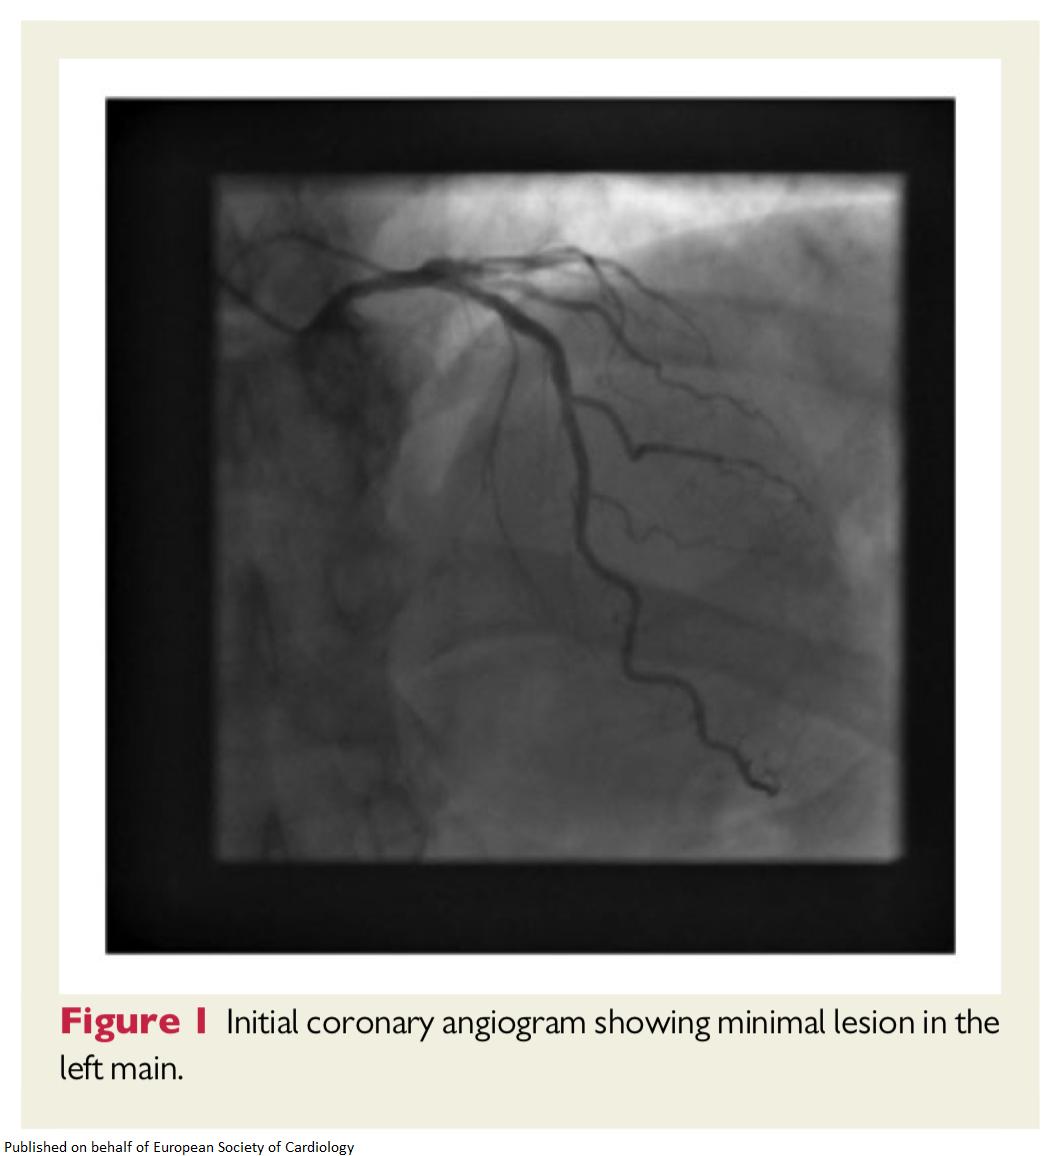

European Society Of Cardiology Journals Detection Of Unexpected Ischaemia Due To Left Main Disease During Tele Rehabilitation Using 12 Lead Electrocardiogram Monitoring T Co 9fvy67uxlv Escardio Johncamm Ehjcasereports Esccot

Pdf Detection Of Unexpected Ischaemia Due To Left Main Disease During Tele Rehabilitation Using 12 Lead Electrocardiogram Monitoring A Case Report